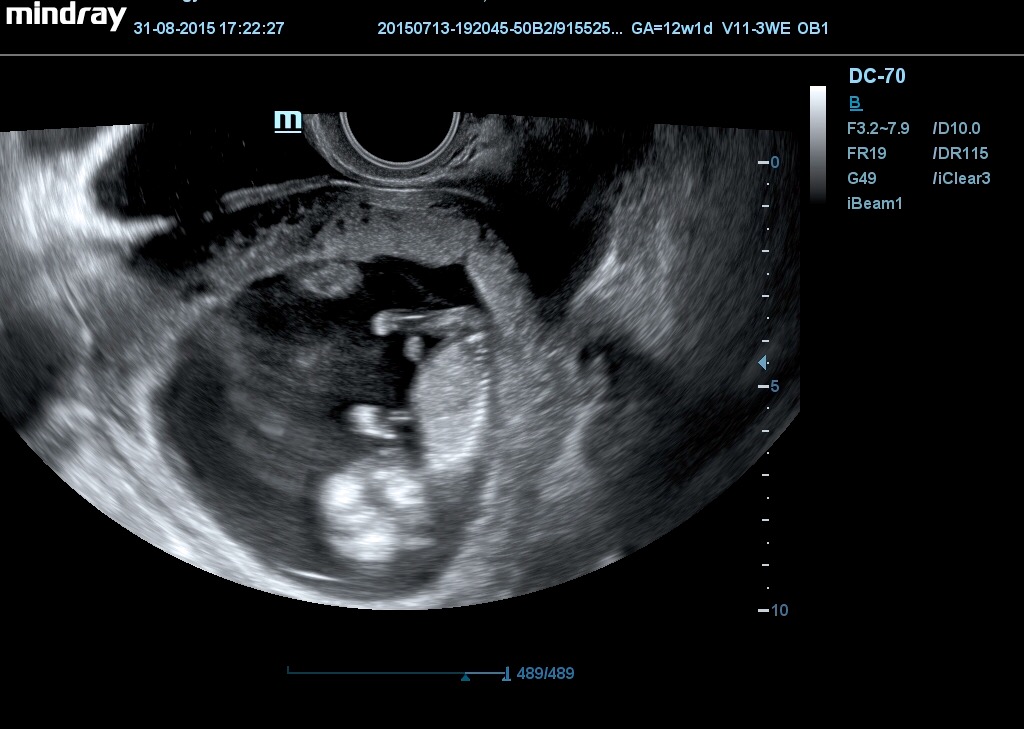

@babydesire spýtam sa,len škoda zo min.piatok mi robil sono tak skoro podle mne nebude... Fakt sa spoliehal na tú genetiku, zo keď ti ma byt hĺbkové sono tak bude sono v dobrej kvalite